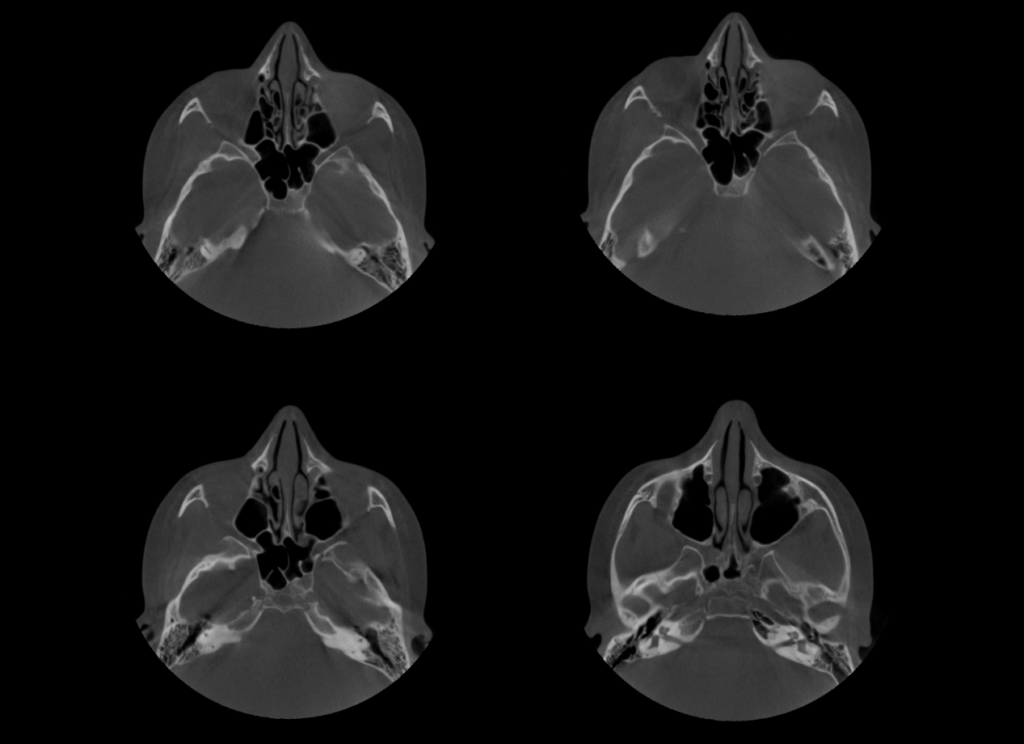

A la evaluación de la tomografía volumétrica (CBCT) en los cortes axiales (Figura 2) y transaxiales (Figura 3), se aprecia imagen hipodensa de forma globular en el interior del cornete medio derecho e izquierdo compatible con Concha Bullosa.

CORTES AXIALES